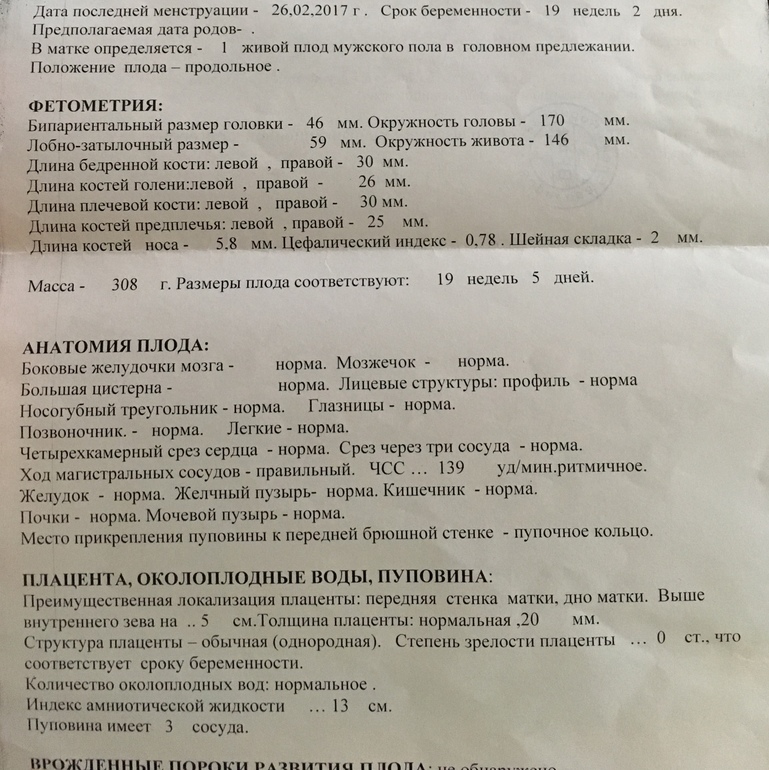

Амнион и Околоплодные Воды: Функции и Роль в Беременности